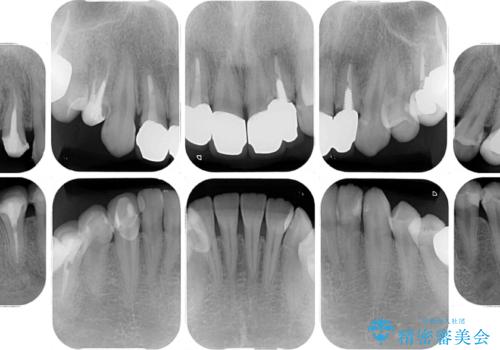

以前の治療箇所が痛む 全顎的なむし歯治療

- 結婚式に向けて、前歯のセラミックを作り替えたいとのことで来院された患者様です。

むし歯で神経を取り除いたことをきっかけに、前歯をセラミックにしたそうですが、金属の縁が見えてきたり、内側に引っ込んでいた歯を強引に前に出しことで汚れが溜まったりと、不具合を感じているとのことでした。

また、奥歯にも痛みがあったり治療途中で放置されていたりと、全顎的な治療が必要な状況でした。

インプラントが必要となった奥歯は、インプラントが埋入できないほど隣の歯の根尖病変が非常に大きかったため、根管治療を行ったうえで半年ほど待ち、骨が再生したことを確認してからインプラントを埋入しました。期間は長くかかりましたが、大変良い仕上がりとなりました。